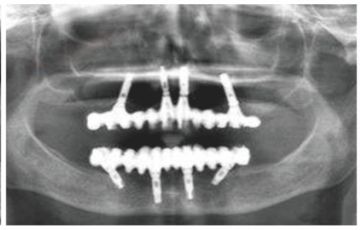

种牙后X光片,未戴冠。

种牙后X光片,戴冠。

通过X光片可以看到,医生虽然尽量设计连冠种植,但还是用了十七个植体,尽管已经是多次调整后的最精简方案,但手术时长依然长达一天。位老先生之前在另一家医院咨询时,医生给的方案是种二十二个植体,光是种植费用就令人大呼“害怕”了。

种植修复后X光片